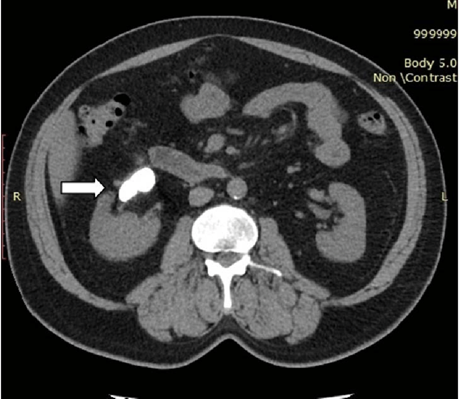

Non-contrast axial CT image showing renal stone.

Ureteric Calculus:

CT KUB axial and coronal sections demonstrating an obstructing right proximal ureteric calculus.

1)Hyperdense focus along ureteric course.

2)Soft-tissue rim sign favors stone over phlebolith.

3) Associated with Upstream hydroureter & hydronephrosis.